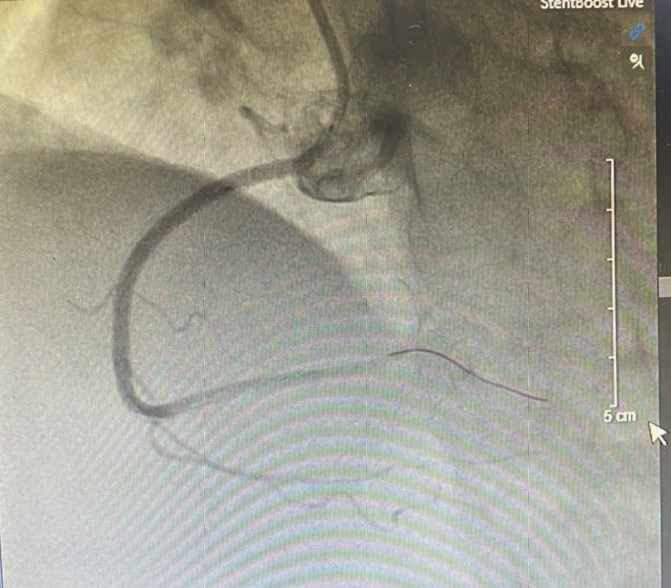

Kết quả chụp mạch vành phát hiện tổn thương nặng 3 thân mạch vành: Tắc hoàn toàn mạch vành phải, hẹp khít liên thất trước và hẹp 80-90% động mạch mũ trên bệnh nhân. Nhận định tổn thương do động mạch vành phải bị tắc hoàn toàn, kíp can thiệp Khoa Tim mạch – Đột quỵ đã nhanh chóng tiến hành tái thông mạch vành phải. Ngay sau khi can thiệp thành công, ghi nhận dòng chảy tốt, bệnh nhân đã ổn định, hết đau ngực. Nhờ được phát hiện can thiệp cấp cứu kịp thời, sử dụng kĩ thuật tiên tiến, đặt stent động mạch vành đã cứu sống bệnh nhân.

- Hình ảnh trước can thiệp